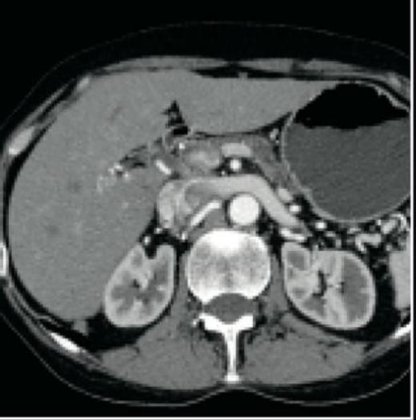

2004 GE LIGHTSPEED 16 SLICE CT SCANNER. Detector channels: 16 x 912. Scan Times:360 degrees, 0.5-0.9 and 1,2,3,4. Slice Thickness mm-0.625, 1.25, 2.5, 3.75, 5, 7.5, 10mm. Gantry Tilt: 30 degrees. X-Ray Tube: 6.3 mHu. X-Ray Generator: 53.2 kW, 10-440 mA’s. Spiral Scanning: yes, Max. scan time: 120 seconds, Max. scan volume: 170 cm. Reconstruction time: 0.1667 seconds. Computer CPU-Open architecture (LINUX). Maximun umber of images displayed at once: 16. Archival Storage: 2.3 GB MOD DICOM 3. CT Angiography: Standard (MiP), and DICOM 3.0 Interface-yes. OPTIONAL: CT Simulation and 3-D Package. This system is available soon. Subject to prior sale.

The used GE Lightspeed RT 16 CT machine is considered one of the world’s leading CT scanners for cancer care. The GE Lightspeed RT 16 CT scanner is a wide-bore system that is easy to operate and features predefined protocols that allow your to perform a wide variety of applications fast and efficiently while delivering exceptional comfort to your patients. This used CT scanner has the power to tackle 3D and 4D imaging as well as display different images simultaneously in real-time..

The refurbished Lightspeed RT 16 is known to be easy-to-use and its ability to display multiple 3D and 4D images simultaneously. The Lightspeed 16 radiotherapy CT is also popular because of its wide-bore opening of 80cm.